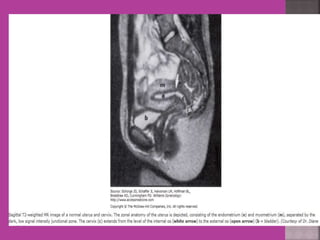

Uterus

Cervix

Vagina

Rectum

Sacrum

Normal- Uterus